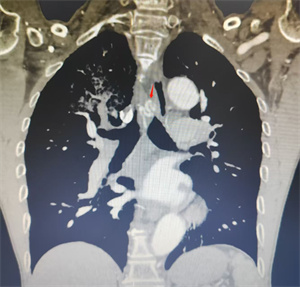

患者周爷爷(化名),71岁,因“咯血3天余”入院,住院期间经药物保守治疗效果欠佳,突发咯血加重(图1),脉氧下降至93%左右,情况危机。介入血管外科会诊后,考虑支气管动脉破裂出血,需立即行急诊BAE治疗。

患者高龄,脉氧偏低,且支气管动脉变异较多,术中超选困难,无疑增加了手术时间,手术难度较大。术前,介入血管外科团队结合患者胸主动脉CTA横轴位及三维重建图像,精准评估出血责任血管的开口位置,有效缩短了术中超选目标血管时间。术中在超选出血责任血管后,采用PVA颗粒联合弹簧圈对出血支气管动脉主干进行精准栓塞,术后造影显示原出血动脉血流消失,手术顺利完成,患者咯血症状得以缓解,术后恢复良好,并于术后第三天康复出院。